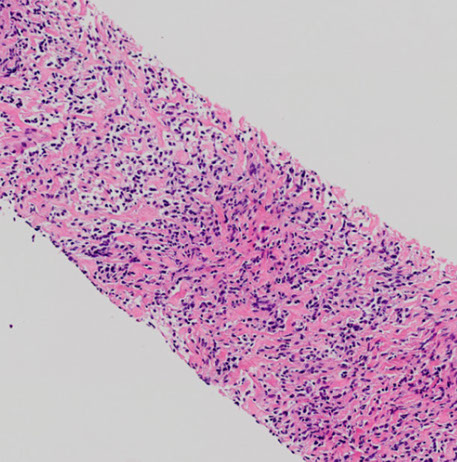

NSIP

Pathology in nonspecific interstitial pneumonia (NSIP)

(A) Cellular pattern, alveolar walls thick c uniform, cellular, inflam interstitial infiltrate; lung architecture preserved. Has small foci of organizing pneumonia

(B) Cellular pattern; cellular infiltrate mostly lymphs and a few plasma cells.

(C) Fibrosing pattern. uniform alveolar walls thickening by interstitial fibrosis; connective tissue appears same age. No honeycombing or fibroblastic foci.

(D) Fibrosing pattern; alveolar wall thickened by dense interstitial fibrosis and few chronic inflam cells; overlying pneumocytes c cuboidal hyperplasia. A few alveolar macrophages are present.

(E) Interstitial fibrosis with airspace enlargement and surrounded by mild to moderate interstitial fibrosis. In contrast to the typical honeycombing of usual interstitial pneumonia, lung architecture is generally preserved. Mucus present within some of these airspaces.

(F) Interstitial fibrosis with airspace enlargement. Bronchioles are dilated. Diameter of larger bronchiole is about 2x that of adjacent muscular pulmonary artery, indicating traction bronchiolectasis. The surrounding alveolar walls are fibrotically thickened but the lung architecture is generally preserved.